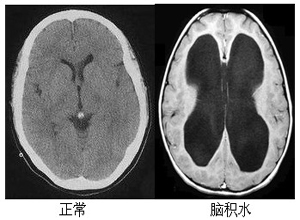

腦積水是非常常見的一種疾病,而且它的危害性是非常大的,尤其是在兒童當(dāng)中患有腦積水的患者是非常多的,那么在成年人當(dāng)中或者是老年人當(dāng)中也會出現(xiàn)腦積水。該病常見的原因有腦外傷、腦腫瘤、腦出血、各種中毒、顱內(nèi)感染、各種腦炎,還有一些先天性的腦積水。那么腦積水能治療嗎?